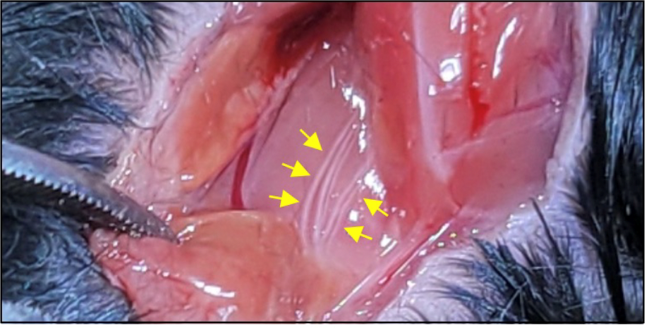

- 연구주제 : 뇌혈관장애-유래 인지기능 저하 및 근감소증 제어기전 연구

- 연구주제 : 뇌경색 동물모델 구축을 통한 뇌혈관 장애 및 염증제어 후보물질 발굴